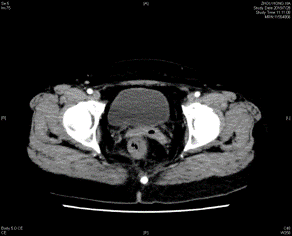

2018-05-08外院 胸部CT提示,两肺多发小结节,考虑转移瘤可能,左肺下叶肺大泡,右肾小结石。2018-5-10外院 全腹CT平扫增强示:直肠中下段肠壁不规则增厚,考虑恶性肿瘤,伴外膜浸润,周围淋巴结显示,左侧盆腔淋巴结肿大。结肠镜示:直肠溃疡性肿块。